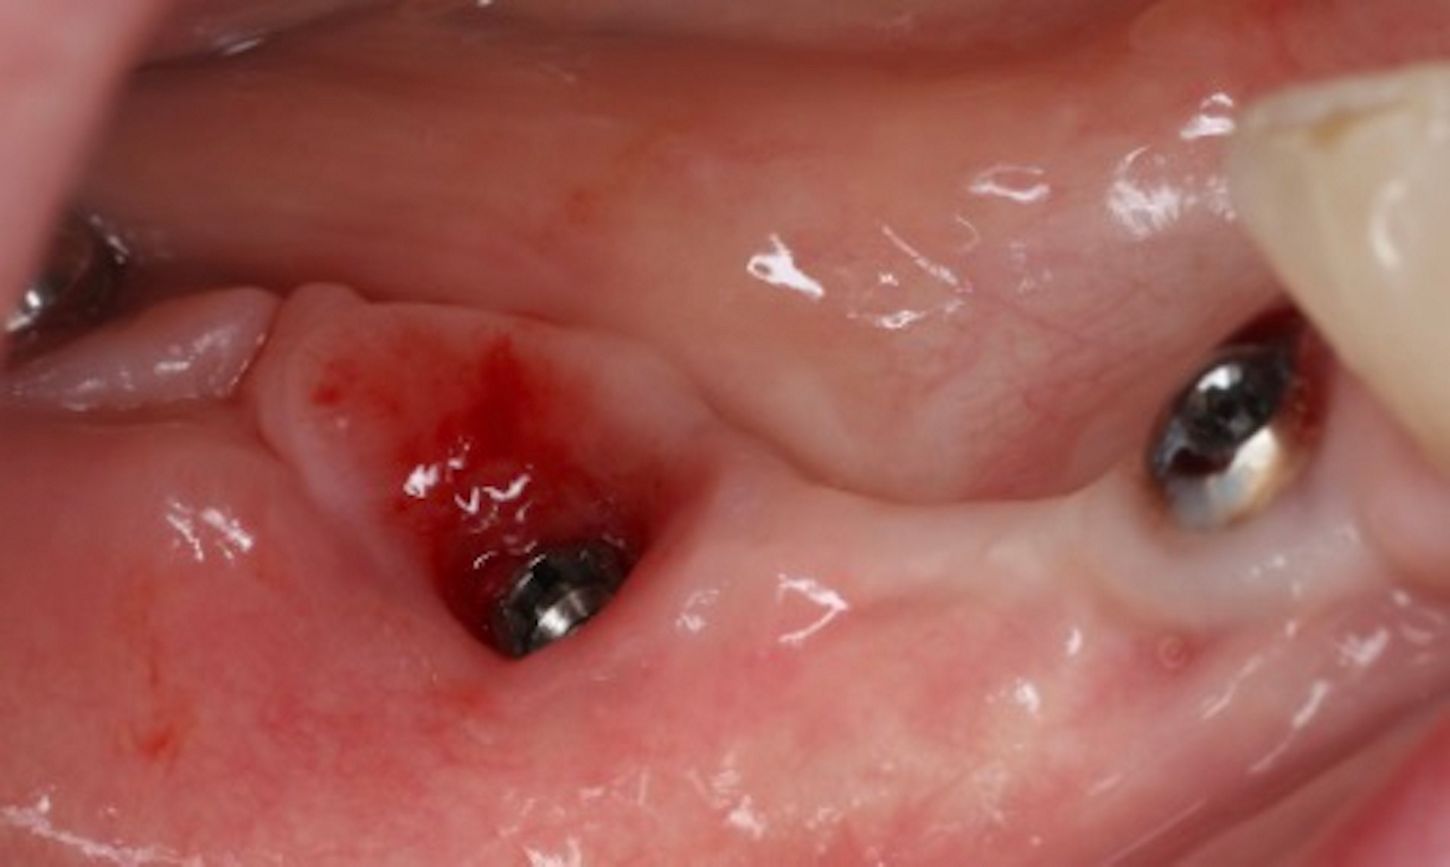

The patient returned in 2020 due to discomfort and bleeding associated with one of the implants. Clinical examination revealed inflammation, bleeding on probing, and suppuration around the implant in site #46. Radiographic evaluation showed both horizontal and vertical bone loss surrounding the implant, indicative of peri-implantitis and progressive bone resorption (Figs. 4,5).

Local anesthesia was administered, and the implant-supported bridge was carefully removed to allow access to the affected area (Fig. 6).

The implant surface at site #46 was decontaminated using the GalvoSurge® electrolytic cleaning system, following the manufacturer’s protocol. The procedure involved the application of an electrolyte solution directly to the implant surface, followed by the activation of a low electrical current. This process generated hydrogen bubbles, which effectively detached the biofilm from the implant surface without mechanical abrasion. The area was then thoroughly irrigated with sterile saline to remove any residual debris (Figs. 7,8)